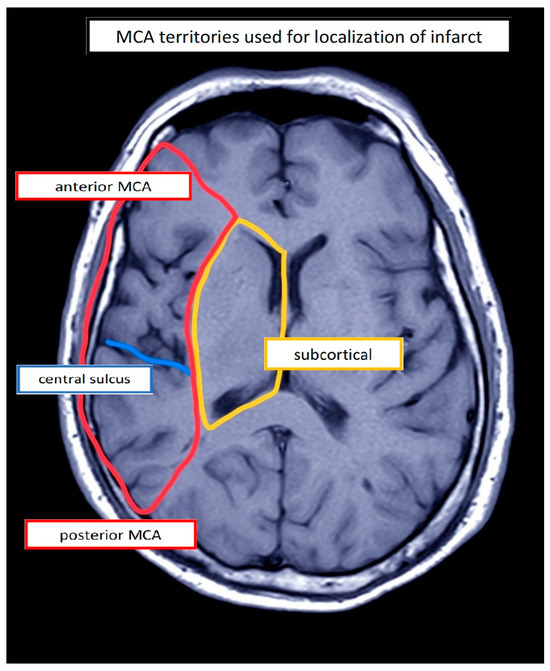

| PwA | Etiology | Lesion Location 1 | Stimulation Site (Left) | Sex | Age (Years) | Education (Years) | Duration (Days) | Assessment | Aphasia 2 | Aphasia Severity 3,4 | Initial Severity (ERBI) 5 (FIM) 6 (−325 to +105) (18–126) | |

| 1 | IS | a/sc | IFG | M | 58 | 18 | 25 | AAT | Wernicke | Moderate 2 | 55 | 102 |

| 2 | IS | a | IFG | F | 82 | 10 | 33 | AAT | Wernicke | Mild | 40 | 62 |

| 3 | IS | a | IFG | M | 70 | 16 | 21 | AAT | Wernicke | Severe | 25 | 68 |

| 4 | IS | sc | IFG | M | 66 | 17 | 57 | AAT | Anomic | Mild | 60 | 86 |

| 5 | IHS | sc | IFG | F | 63 | 16 | 29 | AAT | Anomic | Mild | −15 | 47 |

| 6 | IHS | p/sc | IFG | F | 57 | 17 | 25 | AAT | Anomic | Residual | 40 | 107 |

| 7 | IS | a/p | IFG | M | 69 | 16 | 107 | AAT | Wernicke | Moderate | 50 | 79 |

| 8 | IHS | a/sc | FPC | M | 41 | 16 | 77 | AAT | Anomic | Moderate | −15 | 81 |

| 9 | IHS | p | IFG | M | 64 | 13 | 47 | AAT | Wernicke | Moderate | −65 | 70 |

| 10 | IS | a | IFG | F | 64 | 13 | 13 | AAT | Global | Severe | 5 | 107 |

| 11 | IS | a/sc | IFG | M | 52 | 17 | 32 | AAT | Global | Severe | 35 | 92 |

| 12 | IS | sc | IFG | M | 36 | 12 | 29 | AAT | Global | Severe | 45 | 89 |

| 13 | IS | a/sc | IFG | M | 71 | 13 | 55 | AAT | Broca | Mild | −30 | 53 |

| 14 | IS | a/sc | IFG | M | 48 | 17 | 15 | AAT | Broca | Severe | 60 | 84 |

| 15 | IS | a/p | IFG | M | 73 | 17 | 16 | AAT | Wernicke | Severe | 10 | 93 |

| 16 | IS | sc | IFG | F | 62 | 17 | 46 | AAT | Global | Moderate | −20 | 52 |

| 17 | IS | sc | IFG | M | 50 | 17 | 99 | AAT | Broca | Mild | 10 | 80 |

| 18 | IS | sc | IFG | M | 58 | 10 | 83 | AAT | Global | Severe | 30 | 46 |

| 19 | IS | a | IFG | F | 67 | 10 | 56 | AAT | Anomic | Mild | 15 | 60 |

| 20 | IS | a/p | IFG | M | 66 | 10 | 64 | AAT | Global | Severe | −10 | 47 |

| 21 | IS | a | IFG | M | 69 | 13 | 102 | AAT | Broca | Moderate | −15 | 29 |

| 22 | IS | p | IFG | F | 81 | 10 | 66 | AAT | Wernicke | Severe | 25 | 92 |

| 23 | IS | a | IFG | M | 50 | 16 | 41 | AAT | Broca | Severe | 30 | 81 |

| 24 | IS | sc | IFG | M | 62 | 12 | 24 | AAT | Broca | Moderate | 55 | 95 |

| 25 | IS | a/sc | IFG | M | 60 | 9 | 85 | AAT | Wernicke | Moderate | 5 | 64 |

| 26 | IS | a | IFG | F | 83 | 13 | 31 | AAT | Wernicke | Moderate | 50 | 84 |

| 27 | IS | a/sc | IFG | M | 51 | 16 | 54 | AAT | Wernicke | Moderate | 0 | 90 |

| 28 | IS | a/sc | IFG | M | 80 | 20 | 34 | BIAS-R | Subacute Aph. | Severe 3 | −75 | 78 |

| 29 | IHS | sc | IFG | M | 67 | 13 | 92 | BIAS-R | Subacute Aph. | Severe | −70 | 47 |

| 30 | IS | a/sc/p | M1 | M | 55 | 16 | 99 | BIAS_R | Subacute Aph. | Severe | −20 | 44 |

| 31 | IHS | a/sc | FPC | F | 54 | 17 | 135 | BIAS-R | Subacute Aph. | Severe | −70 | 57 |

| 32 | IS | a/sc | IFG | F | 65 | 10 | 33 | BIAS-R | Subacute Aph. | Severe | −60 | 38 |

| 33 | IS | a/sc | IFG | M | 57 | 17 | 43 | BIAS-R | Subacute Aph. | Severe | −60 | 54 |

| 34 | IS | a/p/sc | M1 | M | 54 | 13 | 50 | BIAS-R | Subacute Aph. | Severe | −125 | 48 |

| 35 | IS | a/sc | FPC | F | 38 | 13 | 144 | BIAS-R | Subacute Aph. | Severe | −65 | 55 |

| 36 | IHS | a/sc | IFG | F | 65 | 17 | 51 | BIAS-R | Subacute Aph. | Severe | −65 | 55 |

| 37 | IS | a/p/sc | M1 | F | 48 | 10 | 85 | BIAS-R | Subacute Aph. | Severe | 40 | 90 |